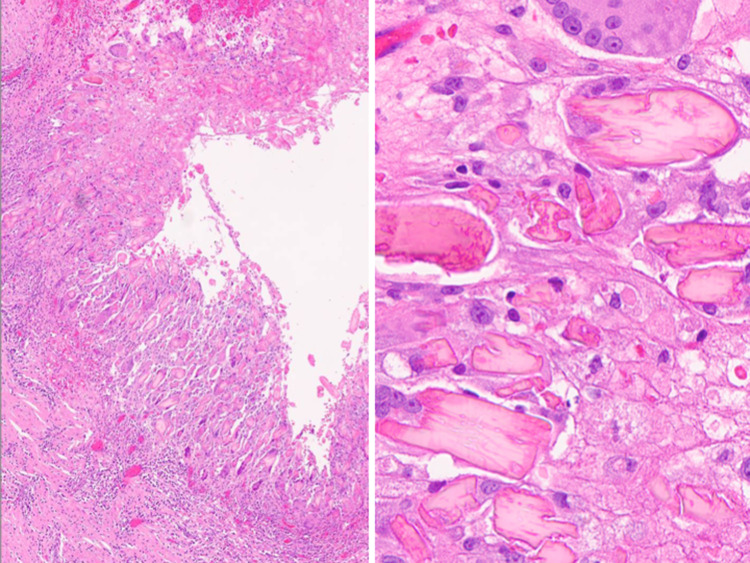

Fig. 13.

(Left) Inflammatory cyst lined by squamous metaplasia (H&E stain, magnification × 40). (Right) FNA of cyst contents from an inflammatory cyst containing scattered atypical metaplastic squamous cells, scant inflammatory cells and numerous orangeophilic crystalloids (Papanicolaou stain, magnification × 60)